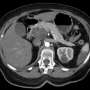

UPDATE: In a groundbreaking development, a newly approved drug is offering renewed hope to patients battling stage 4 pancreatic cancer, a disease notorious for its high mortality rate. Just announced by XYZ Pharmaceuticals, the drug has shown promising results in clinical trials, potentially extending life expectancy for patients like Irene Blair, who was given only six to eight months to live just last June.

This urgent breakthrough comes as pancreatic cancer has long been dubbed one of the deadliest forms of the disease, with survival rates hovering around a mere 10% over five years. The new drug, currently awaiting final regulatory approval, could alter that narrative, making it a focal point for healthcare discussions worldwide.